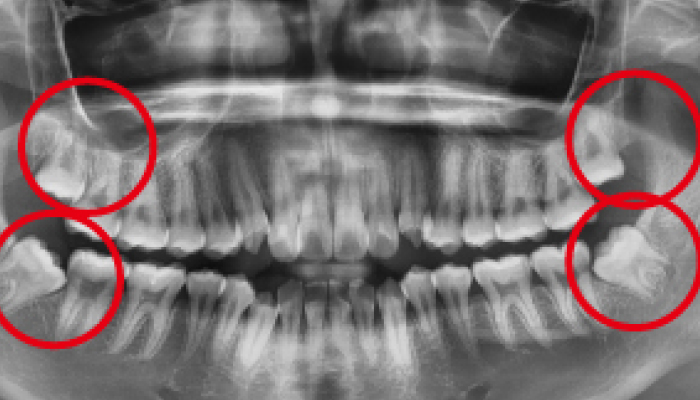

사랑니 발치 전후 사례

• 치료전

치료후